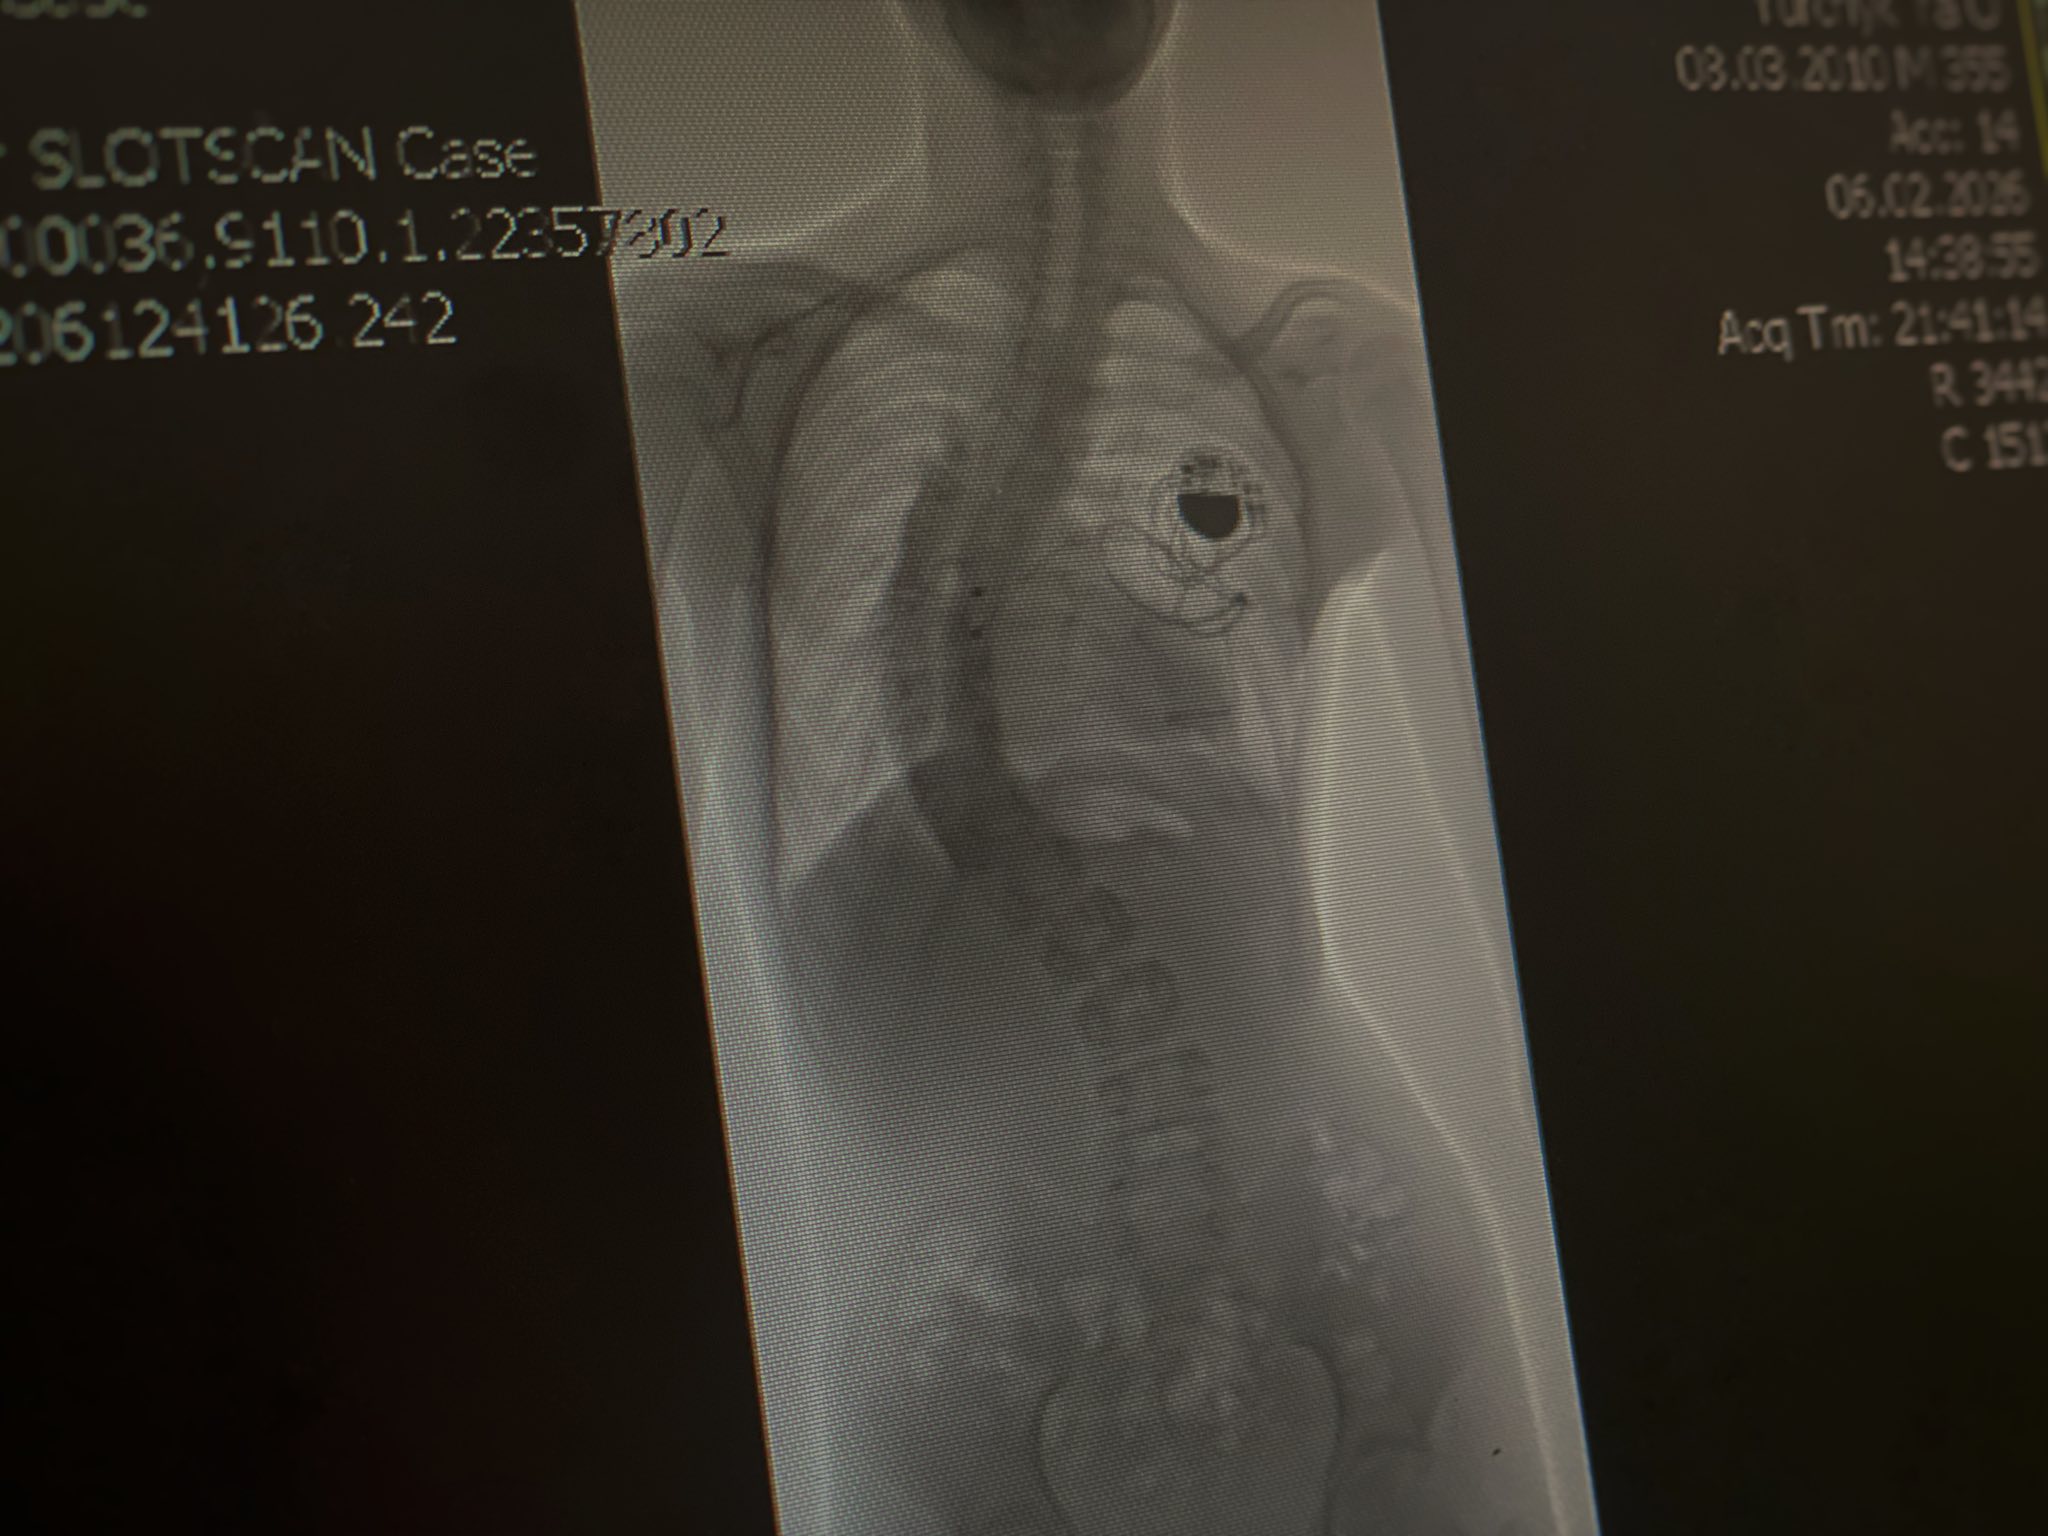

Пацієнт Ярослав із Львівщини від народження мав складні вади серця і ще немовлям переніс кардіохірургічну операцію. З шести місяців він живе з кардіостимулятором, який підтримує серцевий ритм. Згодом у хлопця почав стрімко розвиватися сколіоз — викривлення хребта сягнуло критичних 80 градусів, що спричиняло біль, задишку та суттєві обмеження руху.

Через наявність кардіостимулятора операція була особливо небезпечною: під час втручання використовується обладнання, яке проводить електричний струм через тіло і може порушити роботу пристрою.

Під час операції хірурги спершу обережно відокремили спинний мозок, після чого встановили металеву конструкцію зі стрижнів і гвинтів. Це дозволило зменшити викривлення хребта з 80 до 25 градусів — максимально безпечного рівня.